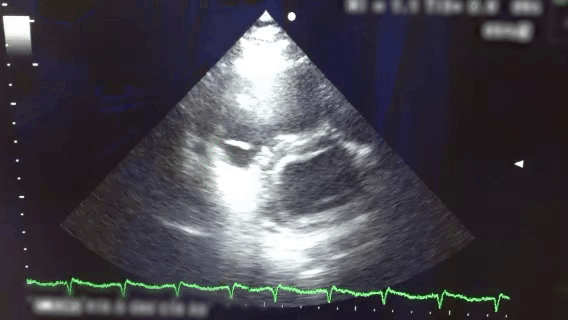

A Patient with Pulmonary Embolism Treated with Systemic Thrombolysis 圖一 Four chamber view-v1 圖一 Parasternal short axis view (已後製 裁切消音)-v1 圖三 Four chamber view (已後製 裁切消音)-v1 圖三 Parasternal short axis view (已後製 裁切消音)-v1 返回 VTE Casebook